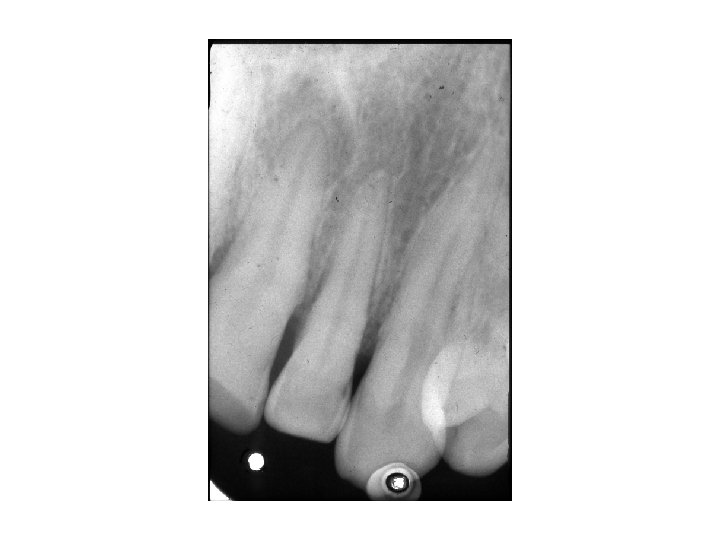

Granuloma periapicale • abgekapselte Ansammlung von Granulationsgewebe • Symptome: Keine Schmerzen, Devitalität des betroffenen Zahnes. • Röntgen: rundliche Form, scharfe Grenze, periapikale Aufhellung • Histologie: Cyst > 1 cm (Fluidum) Granuloma < 1 cm (Granulationsgewebe)